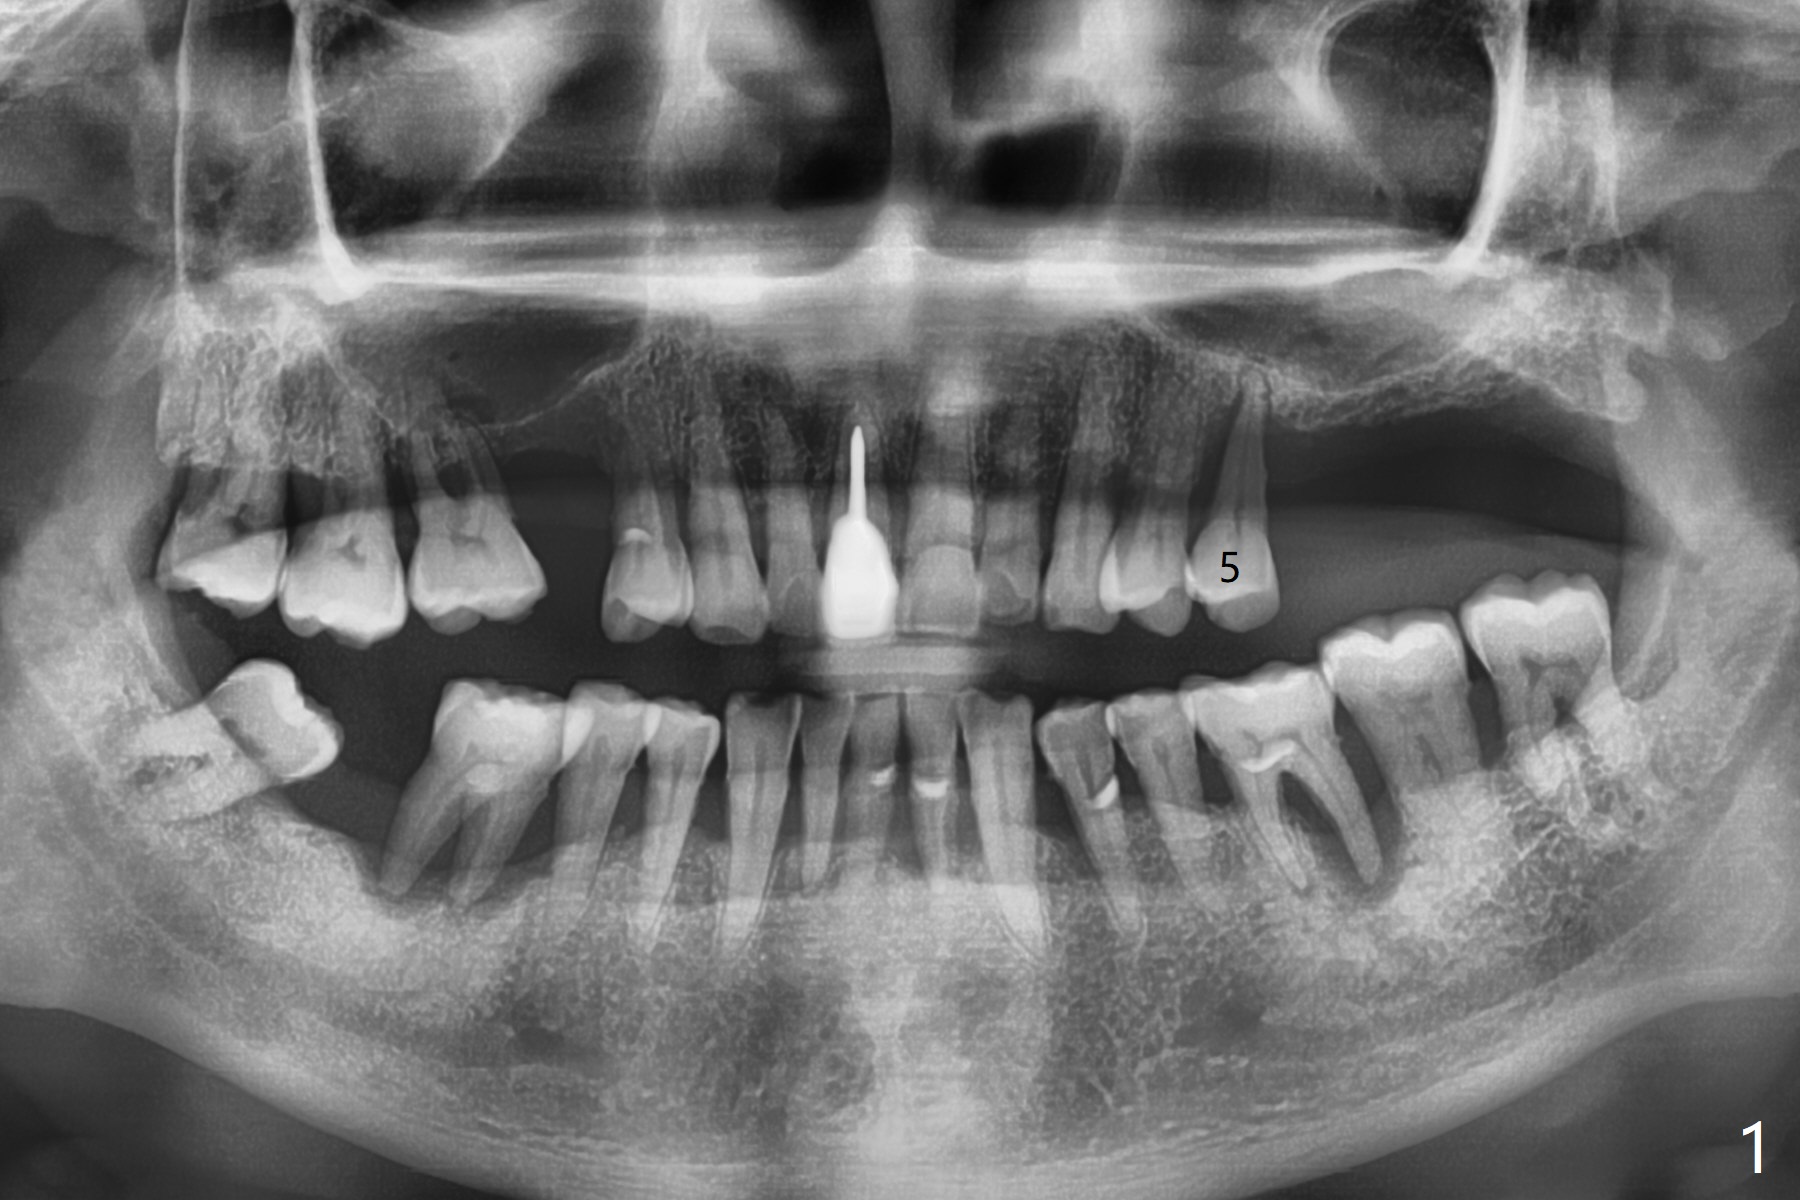

69岁男左上5逆行性(牙周炎导致)牙髓炎(图一)深洗后发展成为不可逆:夜间痛,拔除后植入粘性骨粉(图二:S),将一张PRF膜折叠三层放置牙槽窝开口,使用4-0 PGA缝线,多次figure-8和间断缝合,觉得挺牢靠,就没有使用牙周敷料,后者也估计呆不久。术后严密观察。其实后来伤口愈合正常,但是病人埋怨拔牙造成19号牙疼痛。不过他明天回来拔除30号牙,正好我用完骨粉,但是还有Osteogen Plug和Augma .5 cc 产品, 后者(两者)能维持骨高度吗?